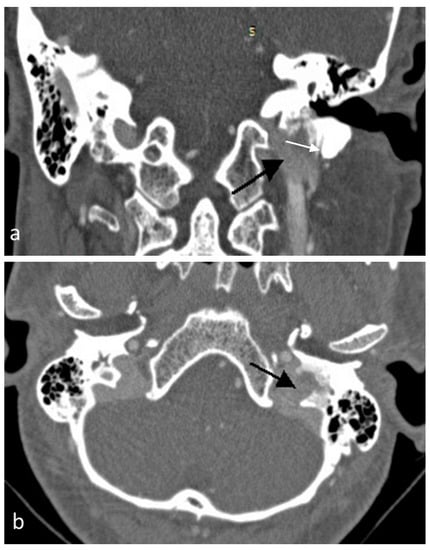

2. Case Presentation